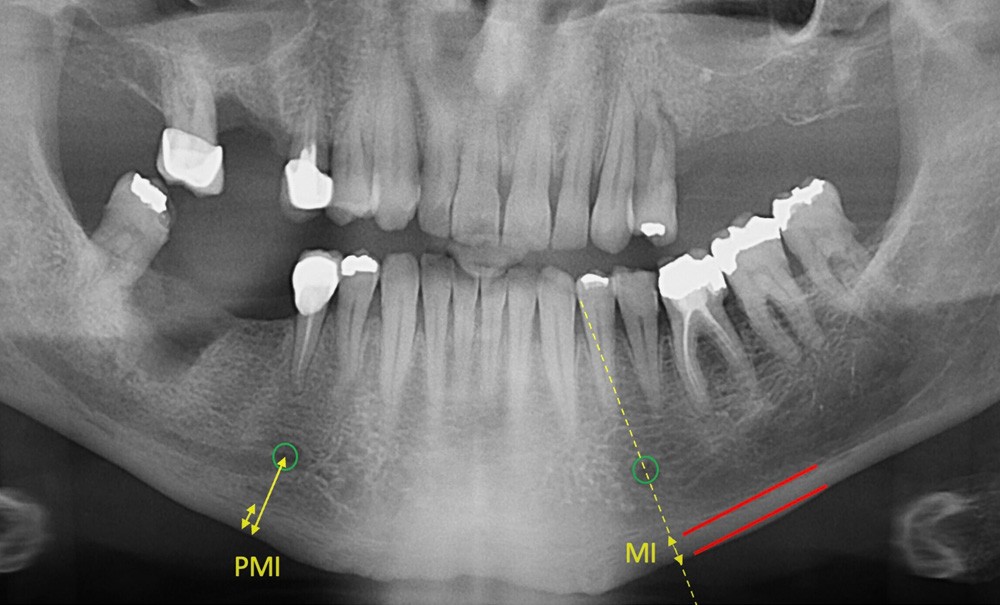

Un biomarqueur se définit comme un indicateur mesurable des processus biologiques physiologiques ou pathologiques. Le projet PANOSTEO propose l’extraction de caractéristiques d’intérêt pour la construction d’un biomarqueur de l’ostéoporose à partir de clichés panoramiques dentaires. L’approche que nous développons a fait l’objet d’un financement Idex Emergence de l’Université Paris Cité et d’un dépôt de brevet.

Un biomarqueur se définit comme un indicateur mesurable des processus biologiques physiologiques ou pathologiques. Le projet PANOSTEO propose l’extraction de caractéristiques d’intérêt pour la construction d’un biomarqueur de l’ostéoporose à partir de clichés panoramiques dentaires.

L’approche que nous développons a fait l’objet d’un financement Idex Emergence de l’Université Paris Cité et d’un dépôt de brevet.